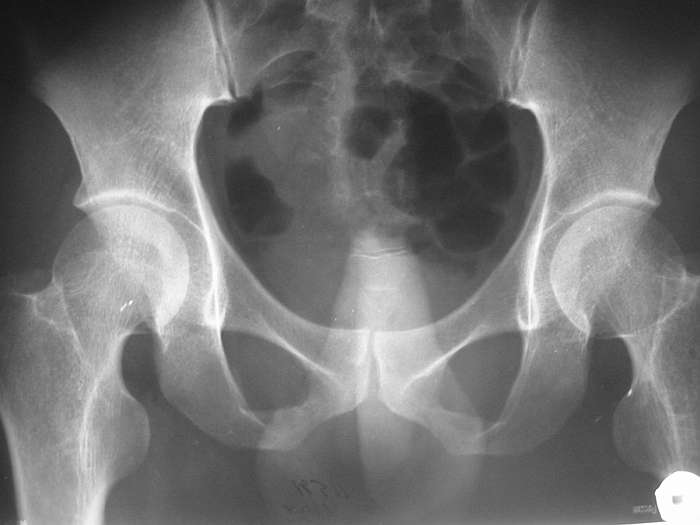

ЗЫ: В приложении снимок таза.